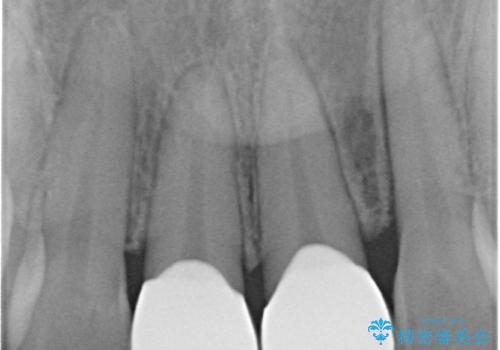

- 前歯の審美性改善と、軽度のがたつきを主訴に来院された患者様です。

マウスピース矯正を行った後、かぶせ物で審美性を改善していきます。

- インビザライン/605,000円 右上1左上1:仮歯/11,000円 ジルコニアクラウン(スタンダード)/121,000円 合計737,000円費用は治療当時の料金となります